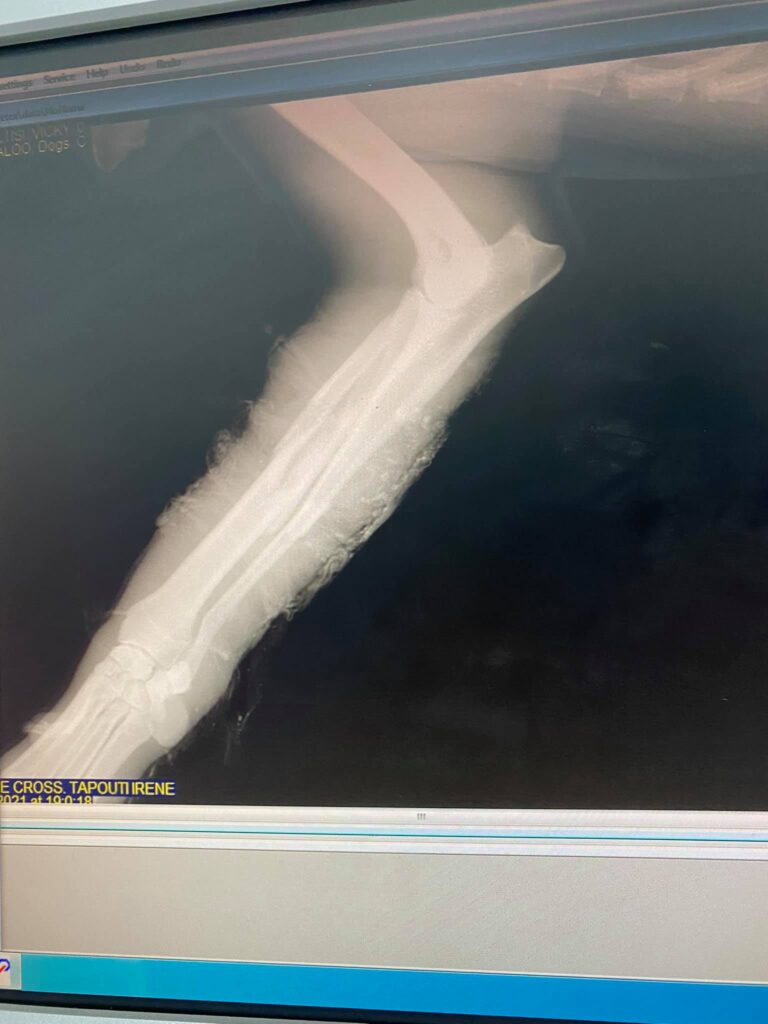

Νεαρό ζώο χτυπήθηκε μετωπικά με όχημα!

Δεν ξέρω ούτε έμαθα ακριβώς πως προκλήθηκε το ατύχημα, αλλά όταν αντίκρισα το σάπιο πλέον πόδι του και τα δόντια του να έχουν μπει μέσα στο στόμα και στα ούλα,ήθελα να κλείσω τα μάτια!

Ο φύλακας το έδεσε με ταινίες για να μην προεξέχουν τα Κόκκαλα..απλά μια δυστυχία!

Το ζώο πέθαινε από σηψαιμία..